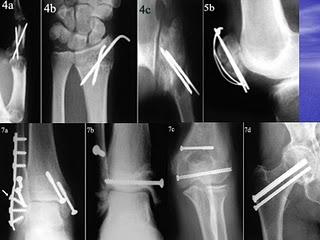

La semana de Trauma sólo tenía 5 días (cuatro de estudio y uno de clase) porque no es una asignatura demasiado preguntada y bastante fácil... o debería serlo, porque a mí me cuesta bastante. Supongo que es por lo poco que me gusta, aunque en la carrera se me acabó dando muy bien, pero he comprobado que es de las pocas asignaturas de las que lo he olvidado casi todo, así que ha sido duro volver a estudiarla prácticamente de cero.